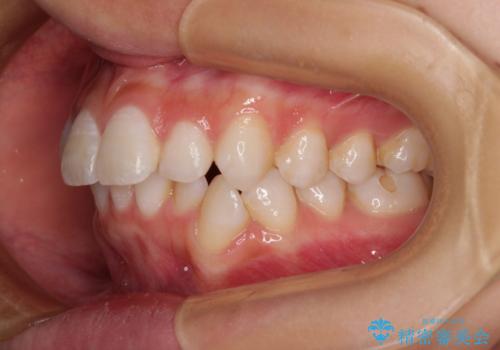

- 口を閉じたときに飛び出してしまう上顎前歯を気にして来院された患者様です。

下顎はデコボコが気になっていたため、上下左右第一小臼歯4本を抜去して、ワイヤー装置にて口元の突出感を改善するよう矯正治療を行うこととしました。

下唇に前歯が当たって跡が残ってしまう状態でしたが、スッキリとした口元に仕上げることができました。